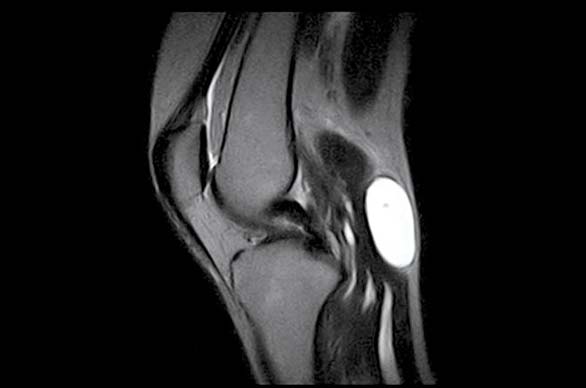

La nostra Risonanza Magnetica con valori di campo statico di 0.5 tesla è stata specificatamente progettata per l’imaging delle Articolazioni: grazie all’ampio campo di vista il sistema permette di studiare, oltre a ginocchio, caviglia, piede, mano, polso e gomito, anche spalla e anca. L’opzione Extended potenzia il sistema MrJ rendendolo in grado di fornire immagini diagnostiche di patologie della colonna cervicale e lombo sacrale.